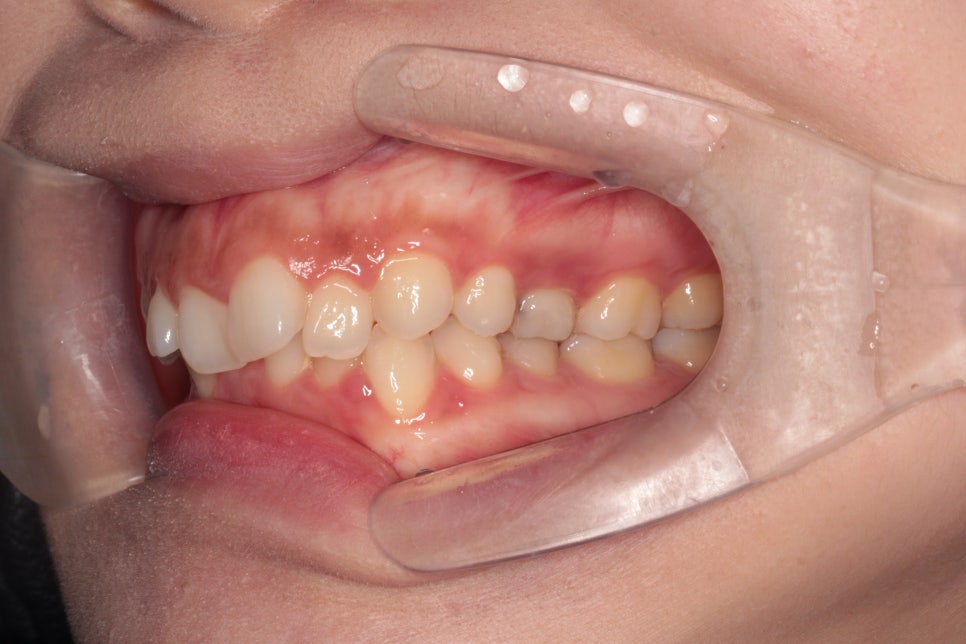

재제작 결정되던 시기의 모습입니다.